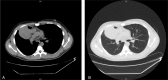

Germ cell tumors (GCTs) represent a well-recognized group of heterogeneous neoplasms with diverse clinical, histopathological, diagnostic, and prognostic characteristics. We present a rare case of a locally aggressive, chemotherapy-resistant immature mediastinal teratoma with a peculiar histological finding of a multilineage somatic-type malignant degeneration. A 21-year-old male patient presented with a 3-week history of persistent, blood-tinged productive cough and shortness of breath. A contrast-enhanced computed tomography (CT) scan of the chest showed a heterogeneous mass occupying the right hemithorax and abutting on adjacent structures. CT-guided biopsy was consistent with immature teratoma. Combination chemotherapy with bleomycin, etoposide, and cisplatin was initiated, albeit without success; the mass showed interval progression in size, and surgical resection through clamshell incision was performed. Histological assessment of the resected mass confirmed the diagnosis of immature teratoma and revealed an extensive multilineage malignant differentiation into sarcomatous, carcinomatous, and melanomatous components. The patient underwent an uneventful recovery but presented 2 months later with extensive liver and bone melanomatous metastases. In this report, relevant findings from the literature are also highlighted. Despite being exceptionally rare, such tumors carry poor prognosis. Understanding the clinicopathological characteristics and biological behavior of such tumors may provide an insight into interventions tailored to improve the otherwise dismal disease outlook.